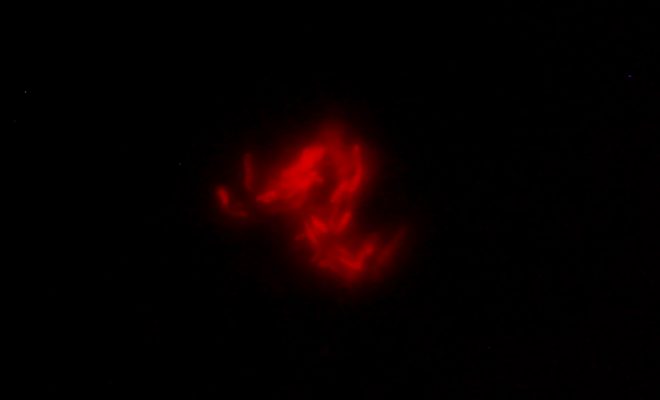

Imagen microscópica de una muestra de esputo de un paciente infectada con el bacteriófago.

“La base de este desarrollo es el trabajo que venimos haciendo desde hace años con bacteriófagos, que son virus que infectan a las bacterias. Lo que hicimos fue modificar genéticamente estos bacteriófagos, introduciéndoles un gen que codifica un reportero fluorescente, de manera tal que cuando se encuentran con la micobacteria que produce la tuberculosis, la infectan, y la bacteria produce una proteína fluorescente. Entonces uno puede verla fácilmente en la muestra de esputo de un paciente utilizando un microscopio”, explica Piuri, directora del Laboratorio de Bacteriófagos y Aplicaciones Biotecnológicas que funciona en el Instituto de Química Biológica de la Facultad de Ciencias Exactas y Naturales (IQUIBICEN, UBA – CONICET).

Si la bacteria se ve en el microscopio de un color rojo fluorescente, eso significa que en el esputo hay Mycobacterium tuberculosis, el agente que produce la infección.

En comparación con las técnicas tradicionales, el procedimiento es sencillo. Se toma una muestra del esputo del paciente, se la somete a un breve proceso para eliminar otros microorganismos que puedan estar presentes en la muestra, y se la pone en contacto con los bacteriófagos modificados. Si la bacteria se ve en el microscopio de un color rojo fluorescente, eso significa que en el esputo hay Mycobacterium tuberculosis, el agente que produce la infección. “Y el resultado –señala Piuri– puede estar disponible de tres a cinco días desde la toma de la muestra”.